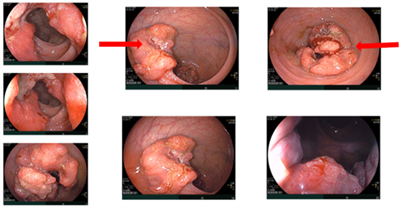

Ca lâm sàng: Điều trị tân bổ trợ ung thư trực tràng giúp giảm giai đoạn và phẫu thuật triệt căn tại Trung tâm Y học hạt nhân và Ung bướu - Bệnh viện Bạch Mai

Ca lâm sàng: Điều trị tân bổ trợ ung thư trực tràng giúp giảm giai đoạn và phẫu thuật triệt căn tại Trung tâm Y học hạt nhân và Ung bướu - Bệnh viện...

Ung thư trực tràng là một trong những ung thư tiêu hóa thường gặp, với chiến lược điều trị dựa trên giai đoạn bệnh, vị trí u (tính từ rìa hậu môn), nguy cơ xâm lấn mạc treo trực tràng và tình trạng...